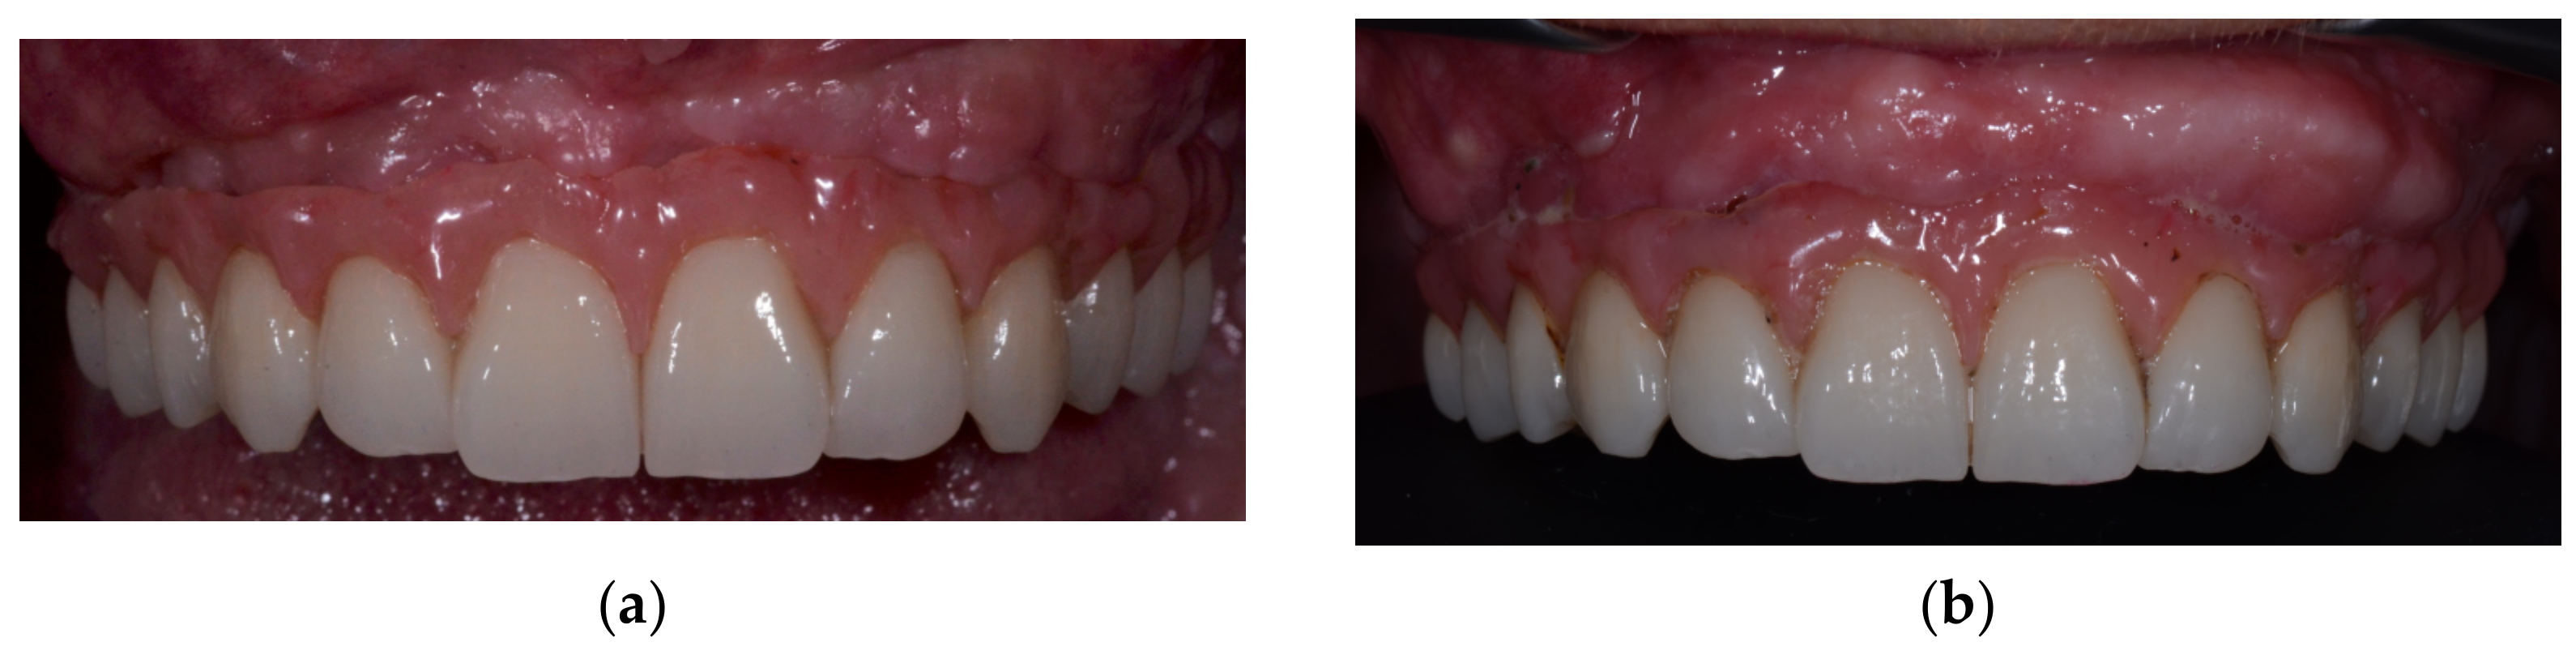

2. Case Report